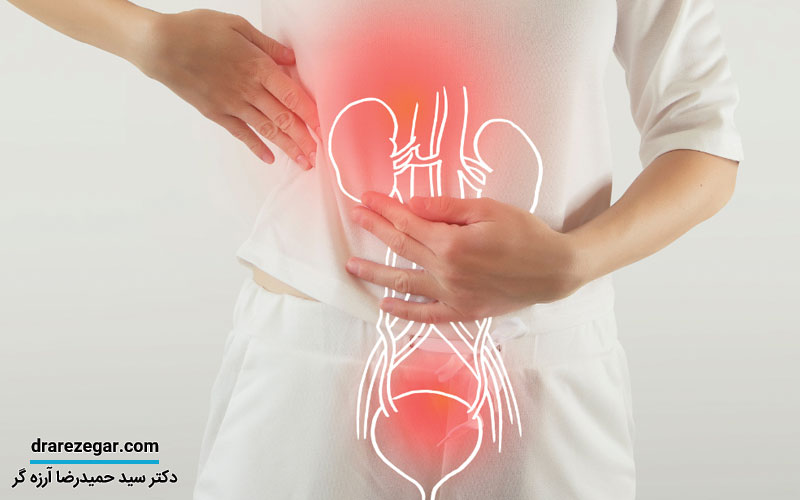

علائم سندرم مثانه دردناک می تواند در افراد مختلف متفاوت باشد. برخی از علائم و نشانه های این سندرم عبارتند از:

- درد یا ناراحتی در ناحیه لگن: این درد ممکن است به صورت مداوم یا متناوب باشد و در برخی موارد می تواند با پر شدن مثانه یا رابطه جنسی شدت یابد.

- احساس نیاز مکرر به ادرار: افراد مبتلا به این سندرم ممکن است احساس نیاز مکرر به دفع ادرار، حتی در مقادیر کم، داشته باشند.

- احساس فوریت در ادرار: احساس فوریت و نیاز فوری به تخلیه مثانه بدون توانایی تحمل ادرار نیز از علائم رایج است.

- کاهش حجم مثانه: برخی افراد ممکن است احساس کنند که ظرفیت مثانه آن ها کاهش یافته و نمی توانند مقدار زیادی ادرار را نگه دارند.

- درد هنگام رابطه جنسی: درد حین یا بعد از رابطه جنسی می تواند یکی از نشانه های این سندرم باشد.

- درد یا سوزش در هنگام ادرار: سوزش یا درد در زمان ادرار کردن نیز یکی از علائم شایع این وضعیت است.